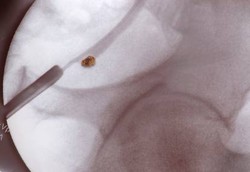

Minum jamu sering menjadi pilihan masyarakat karena dianggap lebih murah dan tanpa efek samping, meski belakangan muncul tudingan bahwa jamu berbahaya bagi ginjal. Namun, ahli herbal menyatakan jamu tidak berbahaya untuk ginjal asalkan tahu syaratnya.